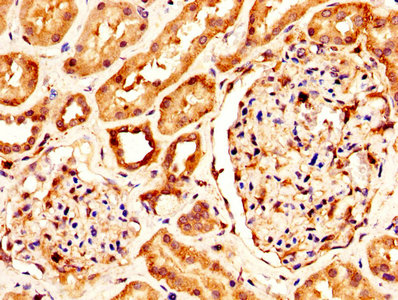

KLK1 Antibody (CSB-PA012446LA01HU)

驗證數據

IHC image of CSB-PA012446LA01HU diluted at 1:300 and staining in paraffin-embedded human kidney tissue performed on a Leica BondTM system. After dewaxing and hydration, antigen retrieval was mediated by high pressure in a citrate buffer (pH 6.0). Section was blocked with 10% normal goat serum 30min at RT. Then primary antibody (1% BSA) was incubated at 4°C overnight. The primary is detected by a biotinylated secondary antibody and visualized using an HRP conjugated SP system.